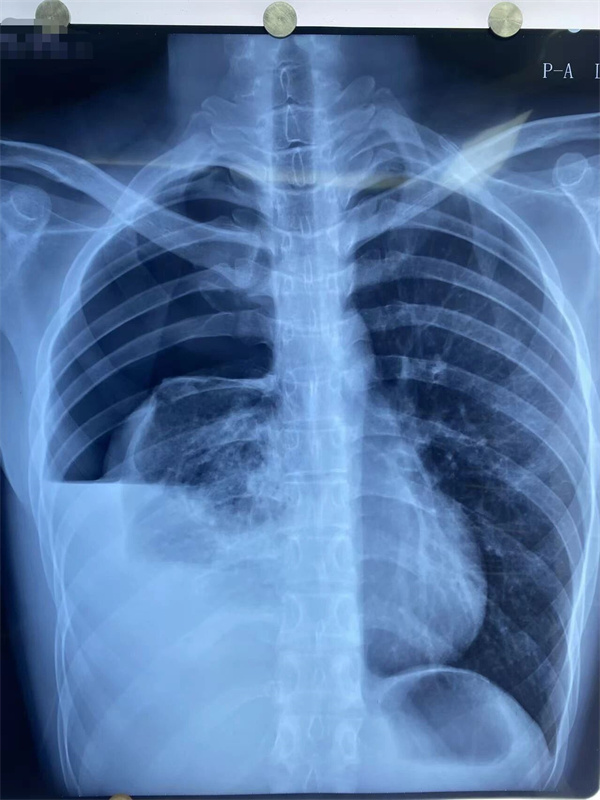

21岁的小王正值大四,一天前日常活动后突然觉得右侧胸闷、呼吸困难,伴右侧胸痛,休息后自觉缓解。第二天患者自觉胸痛及胸闷症状明显加重,校医院胸部X线片提示右侧液气胸,右肺压缩大于80%(如图1),属于典型自发性血气胸。患者经由120紧急送至清华大学附属垂杨柳医院急诊。此时,患者大汗,贫血貌,胸痛无法平卧,胸外科主治医师赵云会诊并请示胸外科主任崔健,明确诊断为右侧血气胸。需尽快手术治疗。